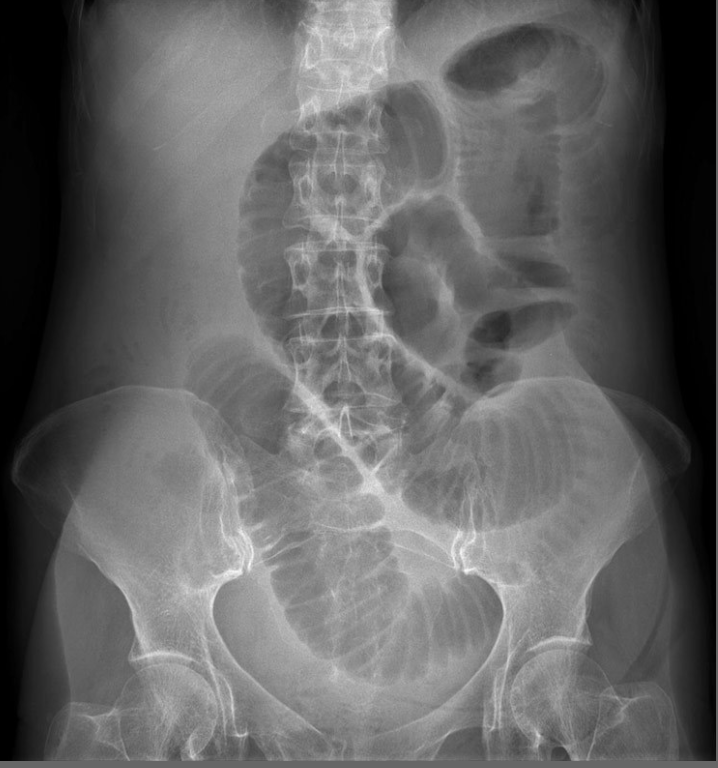

Q

24-year-old patient with suspected appendicitis. What does the image show?

Small bowel obstruction

Dilated loops of bowel with valvulae conniventes – lines crossing the full width of the bowel – indicates small bowel obstruction.